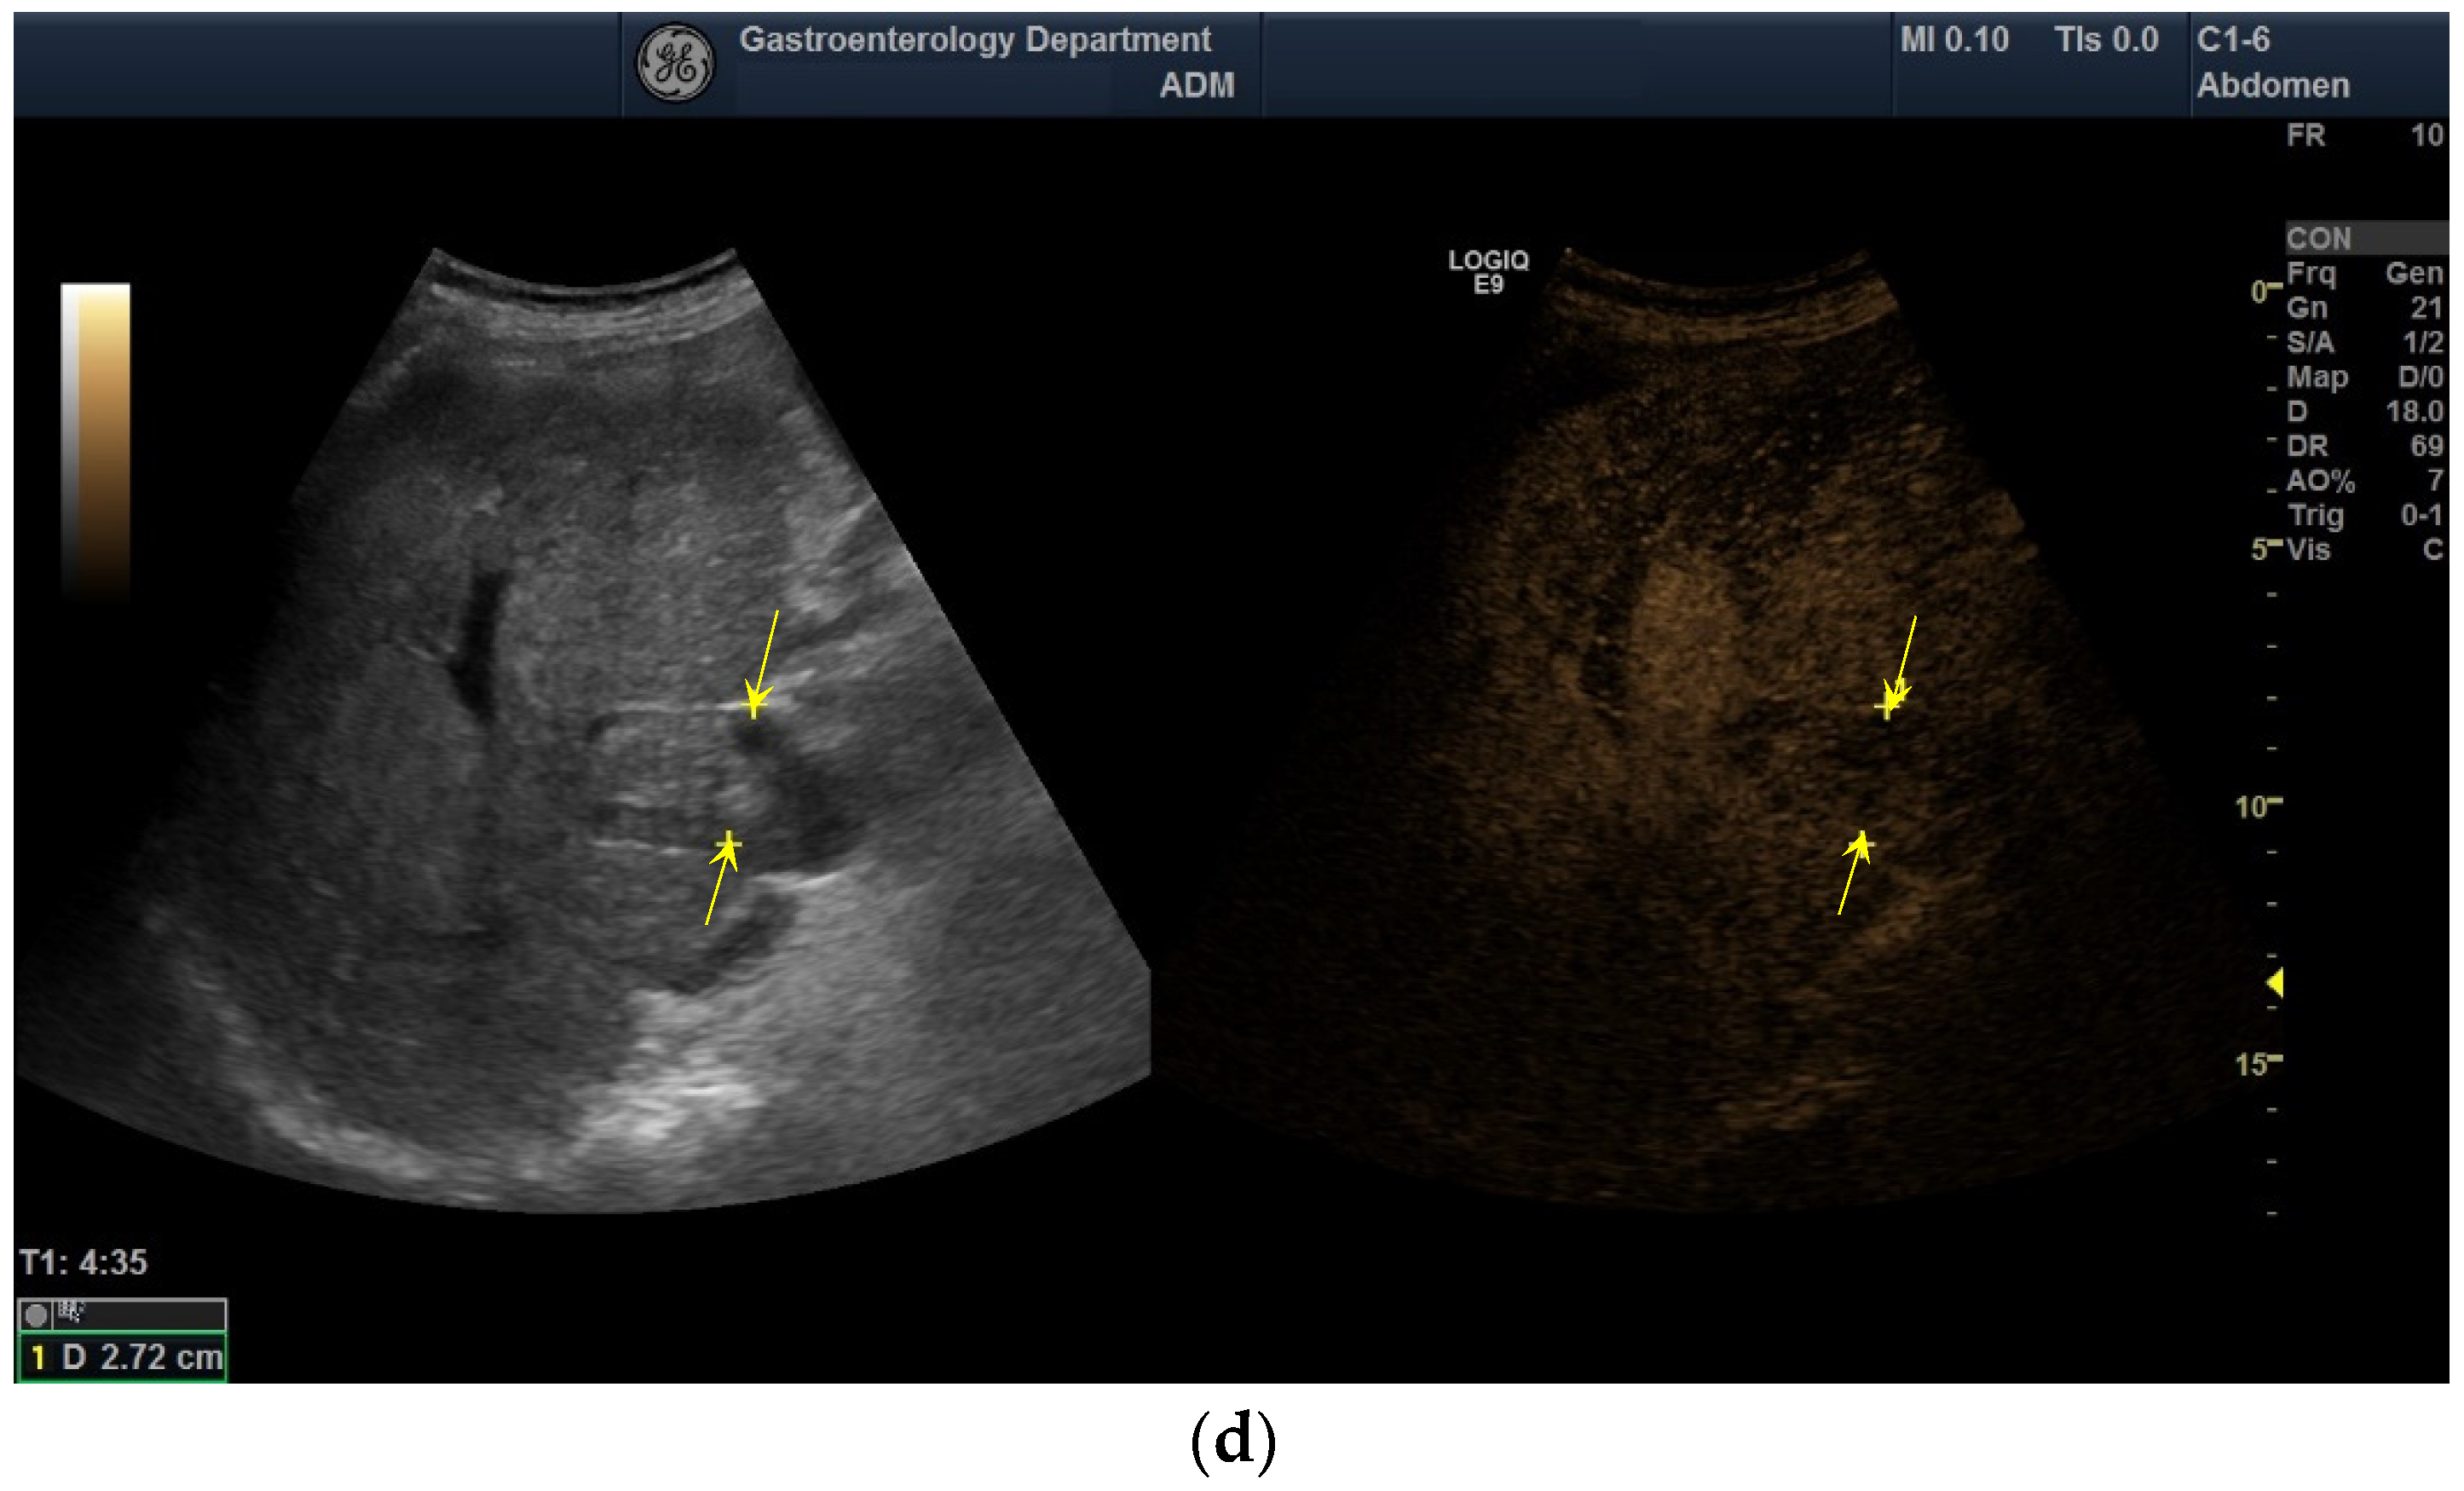

2.3. Diagnostic of PVT

3.5. The Performance of CEUS for the Characterization of PVT